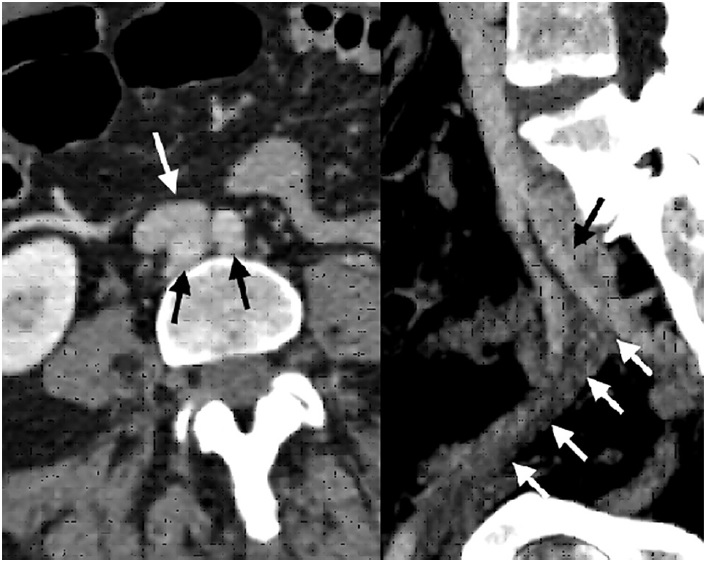

The patient underwent a computed tomography (CT) scan that reported thrombosis of the left internal jugular vein, with occlusion of the left brachiocephalic and subclavian veins (shown in Fig. 1). There was no evidence of collections/abscesses. A brief transthoracic echocardiography was performed in the ER, which rose the suspicion of thrombus/endocarditis. The subsequent transesophageal echocardiogram documented a thrombus adherent to the pacemaker leads. There was an equivocal image of vegetation. Blood cultures, blood panel with C-reactive protein (CRP) and procalcitonin (PCT) were collected. The patient was also scheduled for a repeat CT for evaluation of pulmonary embolism.

Fig. 1 Left. Computed tomography angiography axial section evidencing aortic bifurcation (black arrows), behind the iliocaval junction (white arrow). Right. Sagittal section shows compression by the left hypogastric artery (black arrow) causing external iliac vein thrombosis (white arrows).